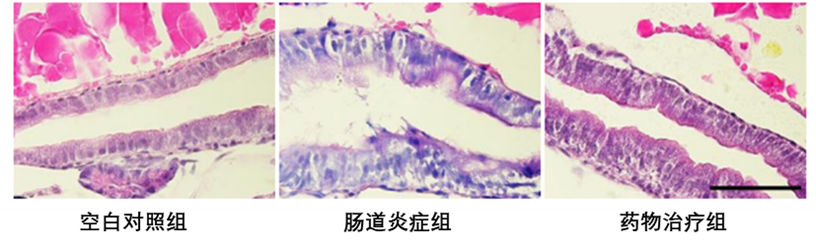

肠道病理组织切片:通过石蜡切片对肠道组织病变进行检测,与对照组相比,肠道炎症组斑马鱼幼鱼的肠道组织松动,肠上皮细胞脱落以及肠腔扩张,在添加供试药物处理后,肠道组织的结构在一定程度上得到了恢复。

肠道黏膜损伤检测:肠道杯状细胞及其分泌的酸性粘蛋白是肠道屏障的重要组成部分,也在维持肠道免疫稳态方面起着重要作用,利用阿尔新兰染色可对肠道中的杯状细胞进行标记。如图中的结果显示,同对照组相比,肠道炎症组中的杯状细胞数量显著减少,提示肠道粘膜受到损伤以及肠道屏障被破坏,而加供试药物处理可使受损的杯状细胞数量恢复。